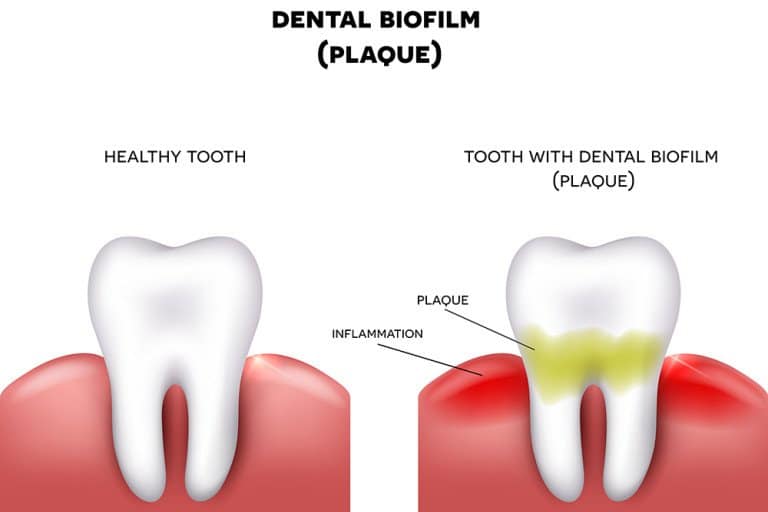

How to build up a tooth. How to build up the perfect tooth todays fda. Instruments known as scalers are used to physically remove the tartar without damaging your teeth or gums. Clean the surface of the tooth with antibacterial liquid.

Removing calcium buildup on teeth. This helps save tooth structure and. How to build up the perfect tooth.